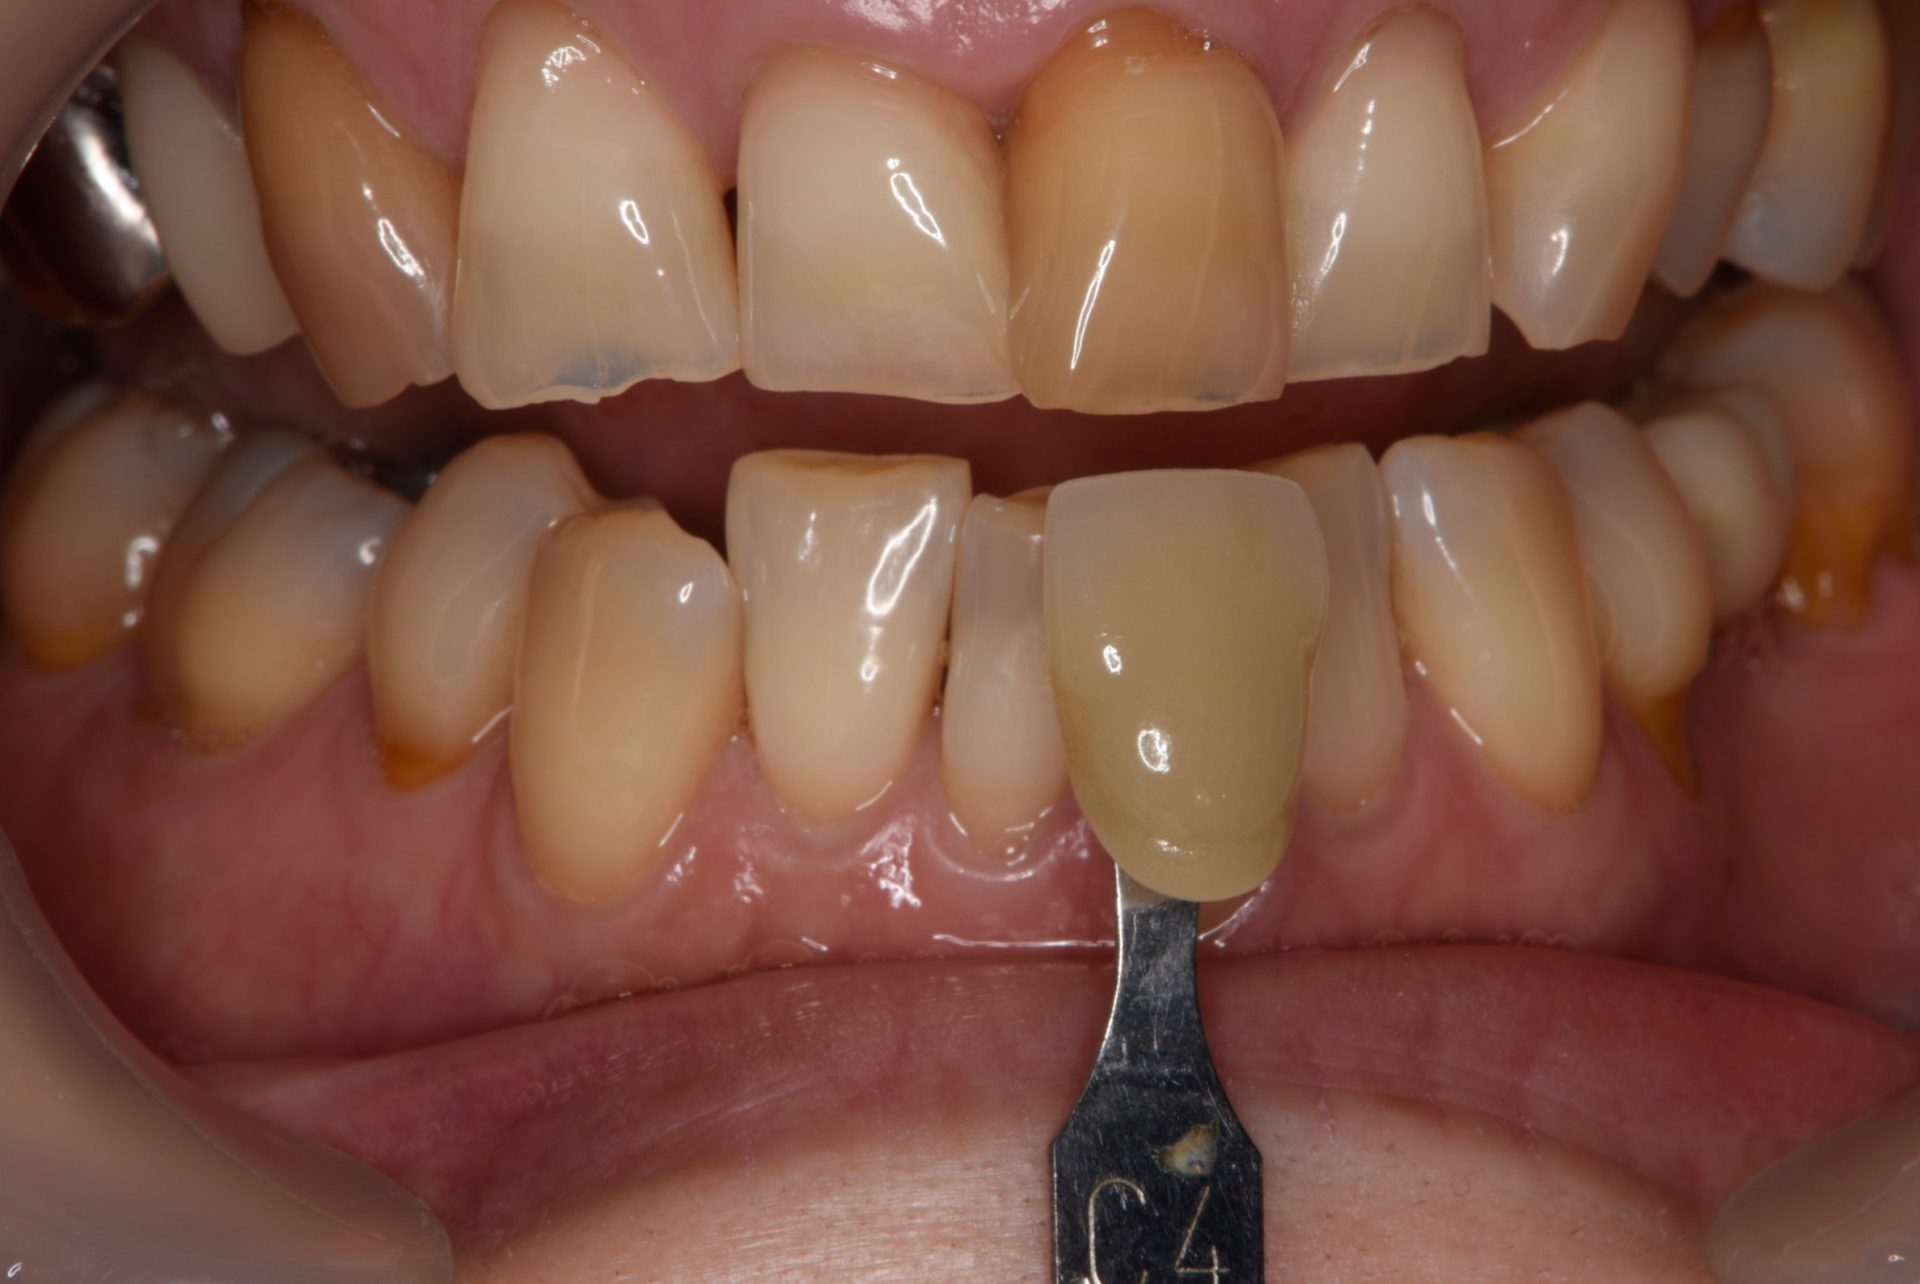

初診時のシェード(色調):C4

これは最も暗い色調です

ウォーキングブリーチ後のシェード:A3.5

周りの歯と比べても気にならなくなりました。

左:A3.5(ウォーキングブリーチ後)

右:C4(初診時)

初診時よりも色調が明るくなっていますね